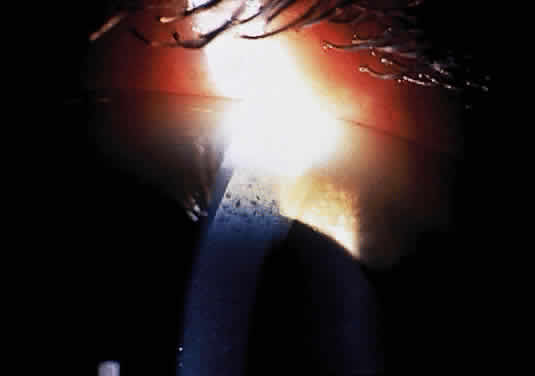

The ocular deposition of glycosphingolipids results in unique and diagnostic eye findings in severely affected hemizygous males and minimally affected heterozygous carrier females.168 The ocular findings have been recognized as one of the distinctive hallmarks of this disease and among its earliest clinical manifestations.169 The corneal opacities appear as whorled streaks from a central vortex and have been called cornea verticillata170,171 (Fig. 16). Bilateral inferior granular anterior capsular or posterior subcapsular lens opacities occur in one third of hemizygous males but rarely in heterozygous females. Mild to severe conjunctival (Fig. 17) and retinal vessel tortuosity are present early in life. Visual acuity is not impaired. However, acute visual loss has occurred in hemizygotes as a result of unilateral central retinal vascular occlusion.171 Other ocular findings include lid edema, myelinated nerve fibers, mild optic atrophy, papilledema, nystagmus, and internuclear ophthalmoplegia.171,172 (Fig. 18). Confirmation of the clinical diagnosis in hemizygotes and heterozygotes requires the demonstration of deficient α-galactosidase A activity in plasma, leukocytes, or tears or increased levels of ceramide trihexaside in plasma or urinary sediment. The diagnosis in female heterozygotes can be established by linkage analysis.163,174 These carriers may have some of the systemic manifestations of the disease, but they usually are milder than in affected males. The most frequent clinical finding in females is the characteristic whorl-like corneal epithelial dystrophy. Corneal opacification in female carriers may be more prominent than in male patients because of the admixture of corneal epithelial cell lines with the normal gene and those with the abnormal gene (lyonization). Abnormal glycosphingolipid deposits are found in all ocular and orbital vessels, in smooth muscle of iris and ciliary body, and in perineural cells and connective tissue of the lids and cornea.175

Fig. 16. Cornea verticillata in a carrier female of Fabry disease. (Courtesy of Irene H. Maumenee, MD)

Fig. 17. Corkscrew-like tortuosity and dilatation of conjunctival vessels in Fabry's disease. (Courtesy of George Spaeth, MD)

Fig. 18. Spoke-like lens changes in Fabry's disease. (Courtesy of George Spaeth, MD)